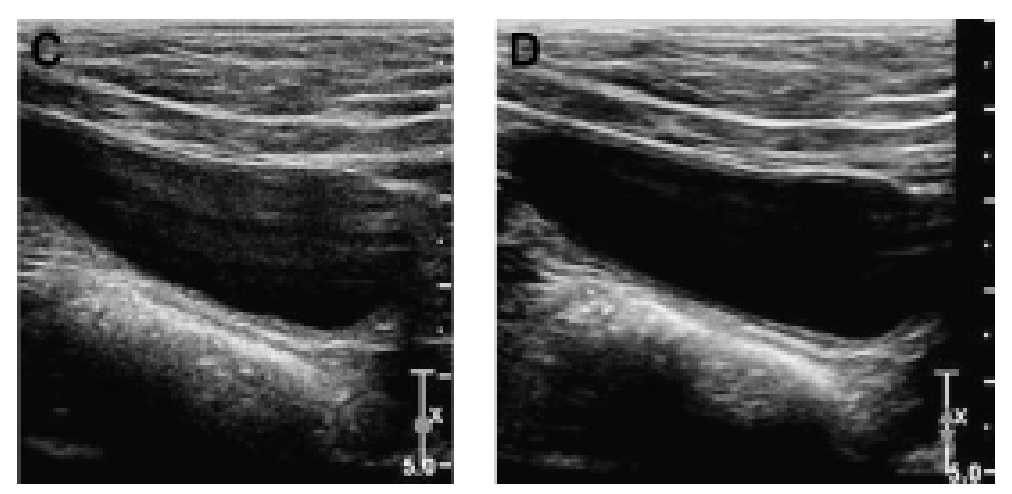

Name this artifact (image on the right)

What is the cause of the artifact? How would you (try to) fix it?

Anisotropy artifact: angle of insonation alters reflective pattern. Normal or hyperchoic when perpendicular; hypoechoic appearance (‘false lesion’) when off angle.

To fix: change the angle of the transducer